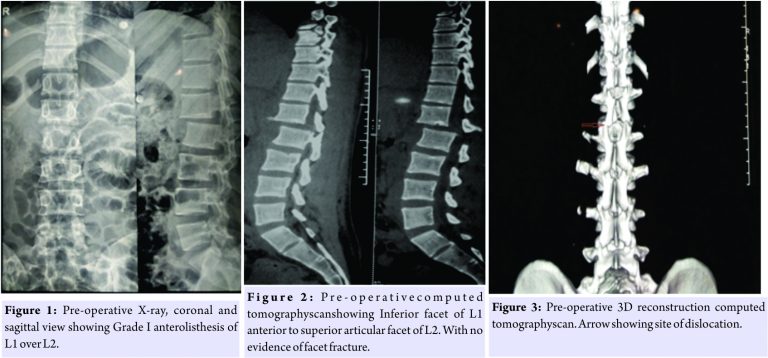

There was no documentation of any steroids given in Andaman local hospital. On his presentation to our institute, he underwent detailed neurological and radiological assessment. Full-length spine X-rays were done to rule out non-contiguous spine injuries in cervical and dorsal spine. On physical examination, there was palpable step at dorsolumbar junction with tenderness of spine at that level. Neurological assessment at the time of presentation shows ASIA Grade A paraplegia with bowel and bladder incontinence with neurological level D12. His lumbar spine radiograph (Fig.1) shows L1-L2 dislocation with Grade IIanterolisthesis of L1 over L2. CT scan (Fig.2 and 3) revealed bilateral facet dislocation, with inferior articular process of L1 located anterior to superior articular process of L2. Magnetic resonance imaging (MRI) imaging (Fig. 4) revealed severe thecal sac and caudaequina nerve roots compression with cord edema at D12 and L1 level. The patient had associated liver laceration with intraperitoneal hemorrhage which was treated conservatively. Since it was a Grade 2 listhesis and since the patient was presented almost a week following injury, it was decided to do two-level stabilization for better leverage of reduction.